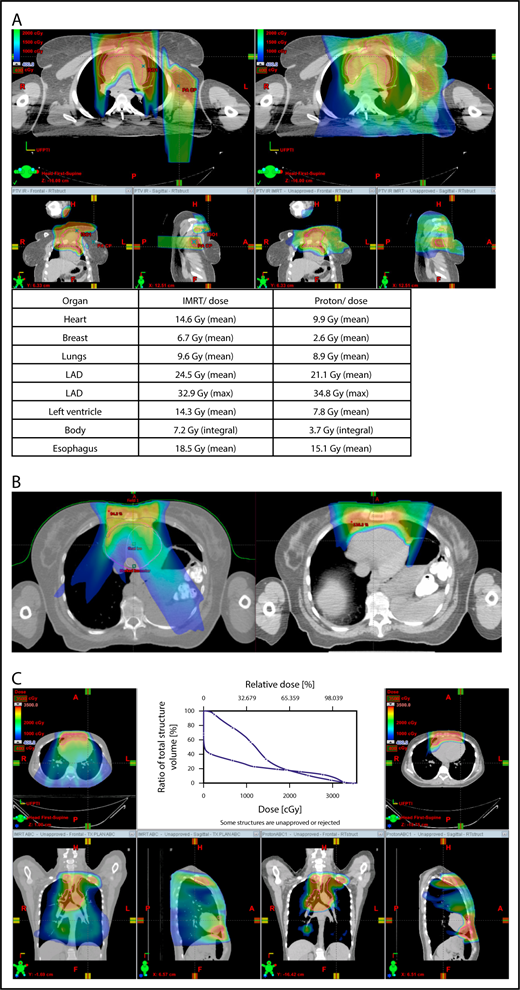

Three scenarios of the relation between mediastinal disease and the heart. (A) Showing how to use the takeoff of the left main stem coronary artery (outlined in pink) to determine the upper and lower mediastinal locations. (B) Scenario 1: coronal CT images of a 28-year-old man with primary mediastinal lymphoma before (i) and after (ii) 6 cycles of rituximab, cyclophosphamide, doxorubicin, vincristine, prednisone (RCHOP) chemotherapy presenting for consolidation with radiation. (Biii) Axial, coronal, and sagittal views of an IMRT plan (upper panels) and a proton plan (lower panels). (Biv) Corresponding mean doses to critical structures using IMRT vs protons. (C) Scenario 2: coronal CT images of a 25-year-old man with Hodgkin lymphoma before (i) and after (ii) 4 cycles of doxorubicin, bleomycin, vinblastine, and dacarbazine (ABVD) chemotherapy presenting for consolidation with radiation. (Ciii) Axial, coronal, and sagittal views of an IMRT plan (upper panels) and a proton plan (lower panels). (Civ) Corresponding mean doses to critical structures using IMRT vs protons. (D) Scenario 3: coronal CT images of a 30-year-old man with recurrent Hodgkin lymphoma as shown in the coronal images of a PET/CT scan (i-ii) presenting for definitive radiation. (Diii) Axial, coronal, and sagittal views of an IMRT plan (upper panels) and a proton plan (lower panels). (Div) Corresponding mean doses to critical structures using IMRT vs protons.

Scenario 2: target spans the right side of the heart

For the targets on the right side of the heart, IMRT often provide comparable doses to the heart and other structures as proton therapy. Notably, however, even when proton plans give a dosimetric advantage over IMRT plans, the magnitude of advantage could vary between cases, and it needs to be judged individually. For example, for the patient shown in Figure 2C, the mean doses to critical structures from proton therapy are sufficiently lower than those from IMRT to suggest that proton therapy may be preferred because of the large volume spanning the right side of the heart. This example illustrates the need for careful consideration of individual cases before deciding on treatment.

Scenario 3: target is on both sides of the heart

Disease that spans significantly in front of the heart anteriorly, posteriorly, or to the left side poses a particular challenge for IMRT; therefore, proton therapy may be the superior plan. Notably, toxicity to the heart and lungs is not eliminated by using proton therapy; rather, the dose to the heart may be lower than IMRT. Thus, for cases like in Figure 2D, clinicians should carefully weigh the therapeutic benefit against the long-term risks for radiation-induced treatment toxicities before deciding on which technique should be used. Indeed, in this case, proton therapy can significantly avoid the heart and should be sought in an attempt to reduce the dose to the heart substructures.